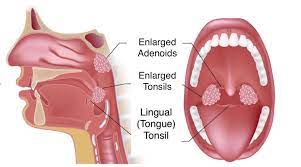

Overview

Package includes:

Days in hospital : 2 to 3 Days (For patient and one attendant)

Days in hotel : 7 Days (For patient and one attendant)

Room type in hospital : Shared

Room type in hotel : Private

Hotel category: Standard

Value added benefits of the Adenoidectomy:

Overview

Package includes:

Days in hospital : 2 to 3 Days (For patient and one attendant)

Days in hotel : 5 Days (For patient and one attendant)

Room type in hospital : Shared

Room type in hotel : Private

Hotel category: Standard

Value added benefits of the Tonsillectomy: